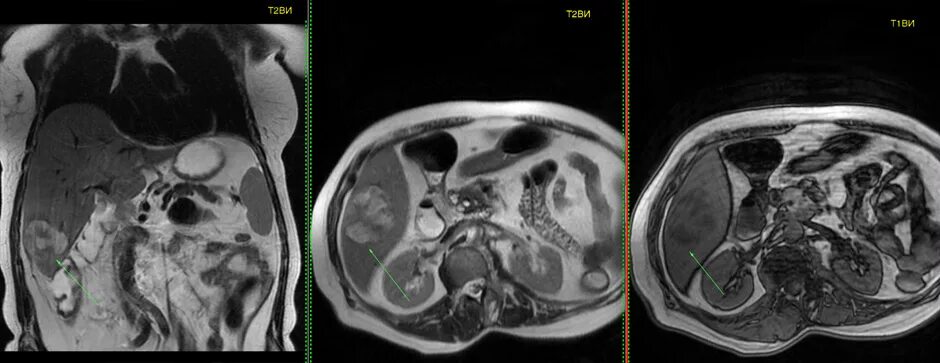

Мскт болюсное контрастирование. болюсное контрастирование при кт. кт с внутривенным болюсным контрастированием. болюсное контрастное усиление при кт.Компьютерная томография с болюсным контрастированием. кт с болюсным контрастированием что это. мскт болюсное контрастирование. спиральная компьютерная томография с болюсным контрастированием.Отечная форма панкреатита кт. кт признаки острого панкреатита. острый панкреатит кт с контрастированием. кт картина панкреонекроза.Томография с болюсным контрастированиемБолюсное контрастирование при кт брюшной полости. хемодектома забрюшинного пространства. кт с контрастом брюшной полости с болюсным контрастированием. эхинококкоз кт с контрастированием.Фазы контрастирования печени мрт. динамическое контрастирование печени мрт. фазы контрастирования при кт. кт с контрастом брюшной полости с болюсным контрастированием.Компьютерная томография с болюсным контрастированием. кт с болюсным контрастированием что это. кт с внутривенным болюсным контрастированием. болюсное контрастное усиление.Кт с болюсным контрастированием что это. компьютерная томография с болюсным контрастированием. методика болюсного контрастирования. кт обп с болюсным контрастированием.Компьютерная томография с болюсным контрастированием. кт перфузия головного мозга. методика болюсного контрастирования.Томография с болюсным контрастированиемТомография с болюсным контрастированиемКт брюшной полости аорты с контрастированием. кт почек с болюсным контрастированием. контрастирование при кт. контрастное усиление при кт.Томография с болюсным контрастированиемТомография с болюсным контрастированиемТомография с болюсным контрастированиемТомография с болюсным контрастированиемОментит кт. компьютерная томография пжж. кт с болюсным контрастированием панкреатит.Кт с болюсным контрастированием что это. компьютерная томография с болюсным контрастированием. кт брюшной полости презентация.Кт огк с контрастированием. скт огу с контрастированием. кт огк, обп с контрастированием. кт с внутривенным контрастированием.Кт с болюсным контрастированием и пэт кт. контрастное усиление при кт обп. кт с болюсным контрастированием что это.Томография с болюсным контрастированиемТомография с болюсным контрастированиемТомография с болюсным контрастированиемТомография с болюсным контрастированиемТомография с болюсным контрастированиемТомография с болюсным контрастированиемТомография с болюсным контрастированиемТомография с болюсным контрастированиемТомография с болюсным контрастированиемТомография с болюсным контрастированиемТомография с болюсным контрастированиемТомограмма брюшной полости кт. кт обп норма. кт брюшной полости и забрюшинного пространства. кт обп с контрастированием норма.Томография с болюсным контрастированиемКт с контрастированием почек онкология. кт ангиография почечных артерий. кт почек с контрастированием норма.Спиральный компьютерный томограф с болюсом. компьютерная томография с болюсным контрастированием. кт с внутривенным болюсным контрастированием.Кт головного мозга с контрастированием. мрт головного мозга с контрастом. кт с контрастом.Мрт обп с контрастом. мрт исследование с контрастированием. кт с контрастированием. кт брюшной полости с контрастом.Томография с болюсным контрастированиемКт с контрастированием брюшной полости контрастированием органов. кт почек с болюсным контрастированием. кт обп с болюсным контрастированием. томограмма брюшной полости кт.Кт ангиограмма. кт ангиография с контрастированием. кт-ангиография артерий нижних конечностей.